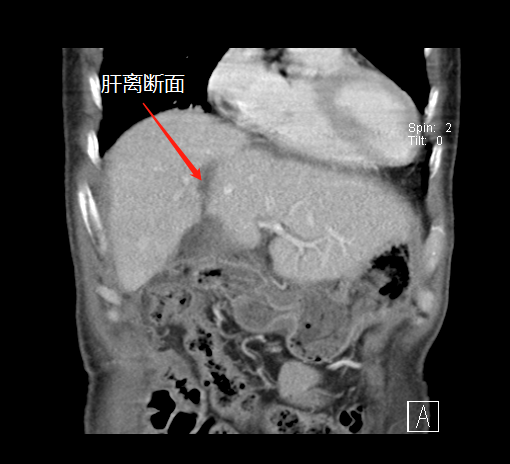

左肝增生,第二次手术切除肿瘤

经过20天左右的“养肝”,经CT复查显示,患者的左侧肝脏体积已增长至42.8%,这时候,也就达到了我们说的“养大好肝、再切病肝”,因为此时好肝已经足以维持患者身体的运转需要。

二次手术完整切除肿瘤

于是,专家团队便于10月中旬为患者实施了第二阶段肿瘤切除术,在此过程中,由于患者同时合并腹茧症,通过第一次手术的刺激腹腔内粘连非常严重,手术遭遇了巨大的困难,最后经过近7小时左右的艰苦奋战,攻坚克难,终于完整切除了患者右肝的巨大肿瘤,手术取得了成功,患者重获新生。